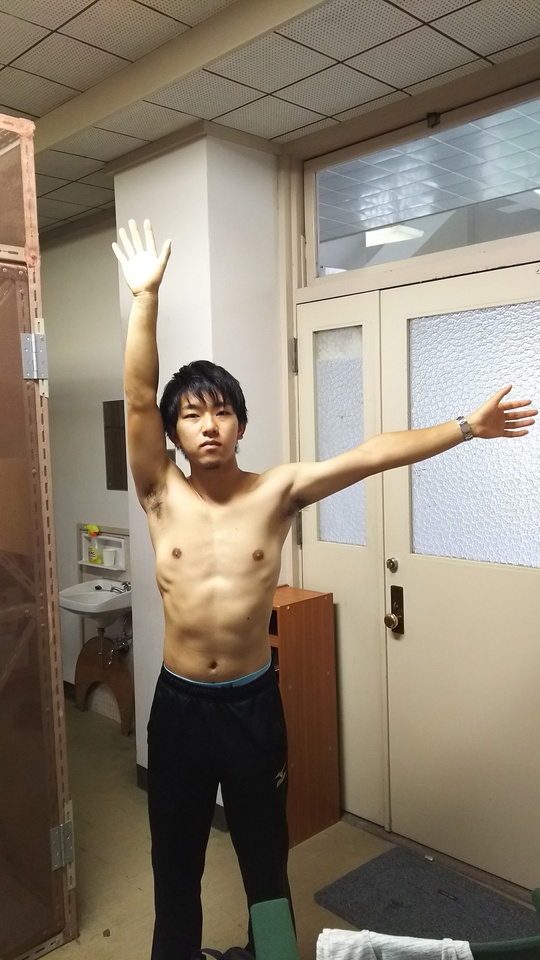

大学3年生アーチェリー選手、2017年3月から弓を肩の高さに引き上げて保持できなくなる。腫れ、熱は無いが腕を横から挙げていくと60度蚊ら90度で痛みが生じ、120度以上は力が入らず180度腕が挙がらない。

近隣医科に行くほど日常生活にも支障なく放置して様子を見ていたが、症状不変。

棘上筋への置鍼(寸3、2番)、その後筋膜リリース3分間。施術時間7分間ほど。

直後効果として、ROM左右さ無く、上肢拳上に支障なし。その2週間後、施術後の状態が維持され、アーチェリー完全復帰。

骨・軟骨・靭帯損傷・神経損傷なく、筋・筋膜・腱の支障による症状の場合は可逆的変化は著明。物理刺激は即時反応を示すが、物理刺激をやめれば反応は消失するのが一般的である。しかし、本症例のように約6か月にも及ぶ傷害であっても、即時効果ならびに持続的効果が確認できた症例である。